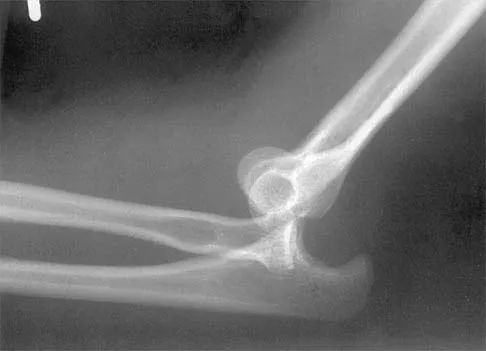

Figure 38 shows the radiograph of a 16-year-old wrestler who injured his elbow when he was thrown to the mat by his opponent. To minimize additional trauma to the medial soft tissues, the elbow should be reduced in

Explanation